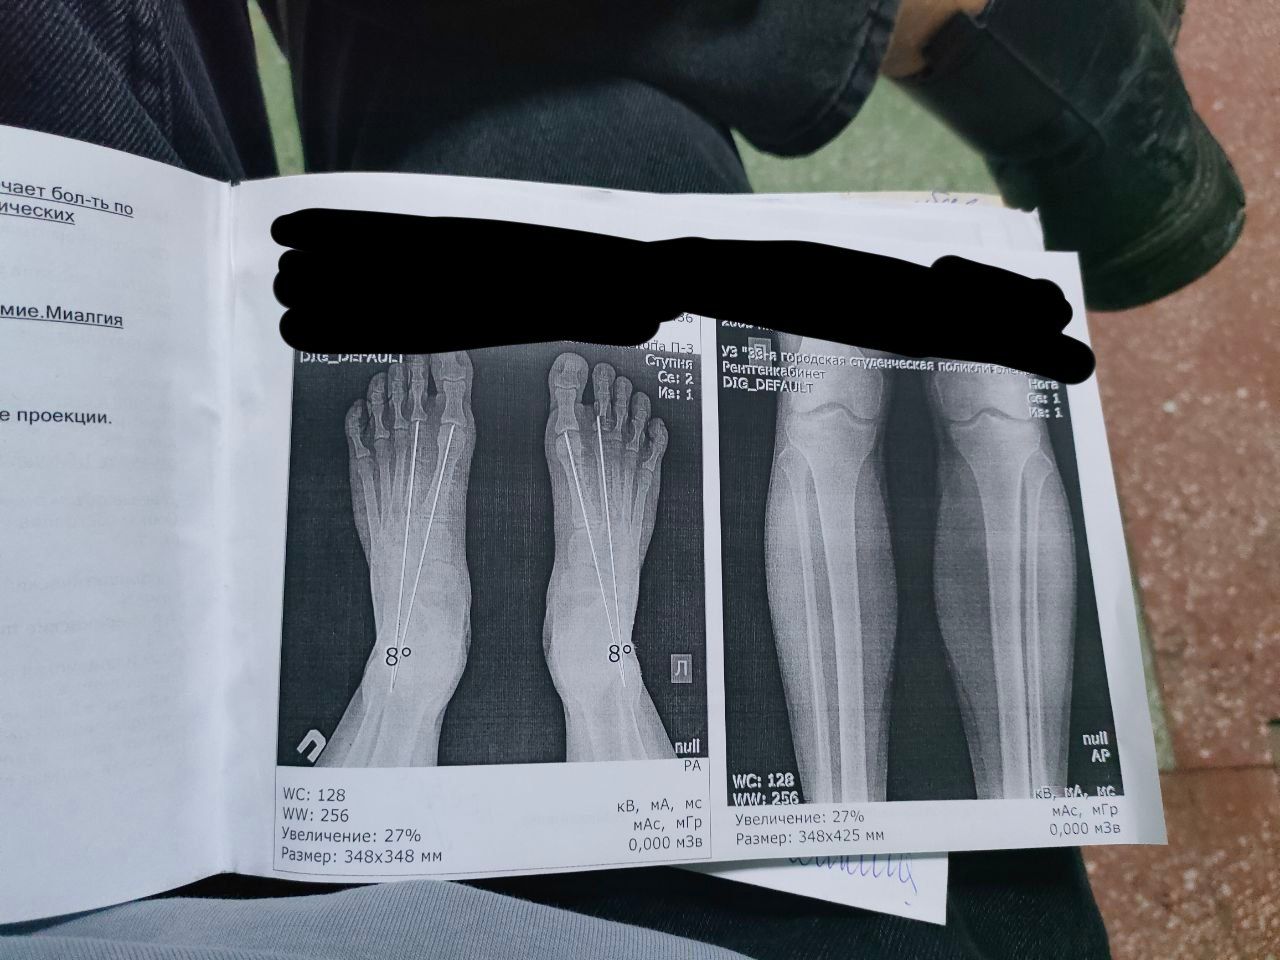

Здравствуйте,могу ли рассчитывать на категорию годности В по коксартрозу или категории годности Д по полой стопе.

2. По полой стопе присвоят призывную категорию годности "А", так как степень её деформации не является умеренно выраженной и не сопровождается незначительным болевым синдромом с нарушением статики.